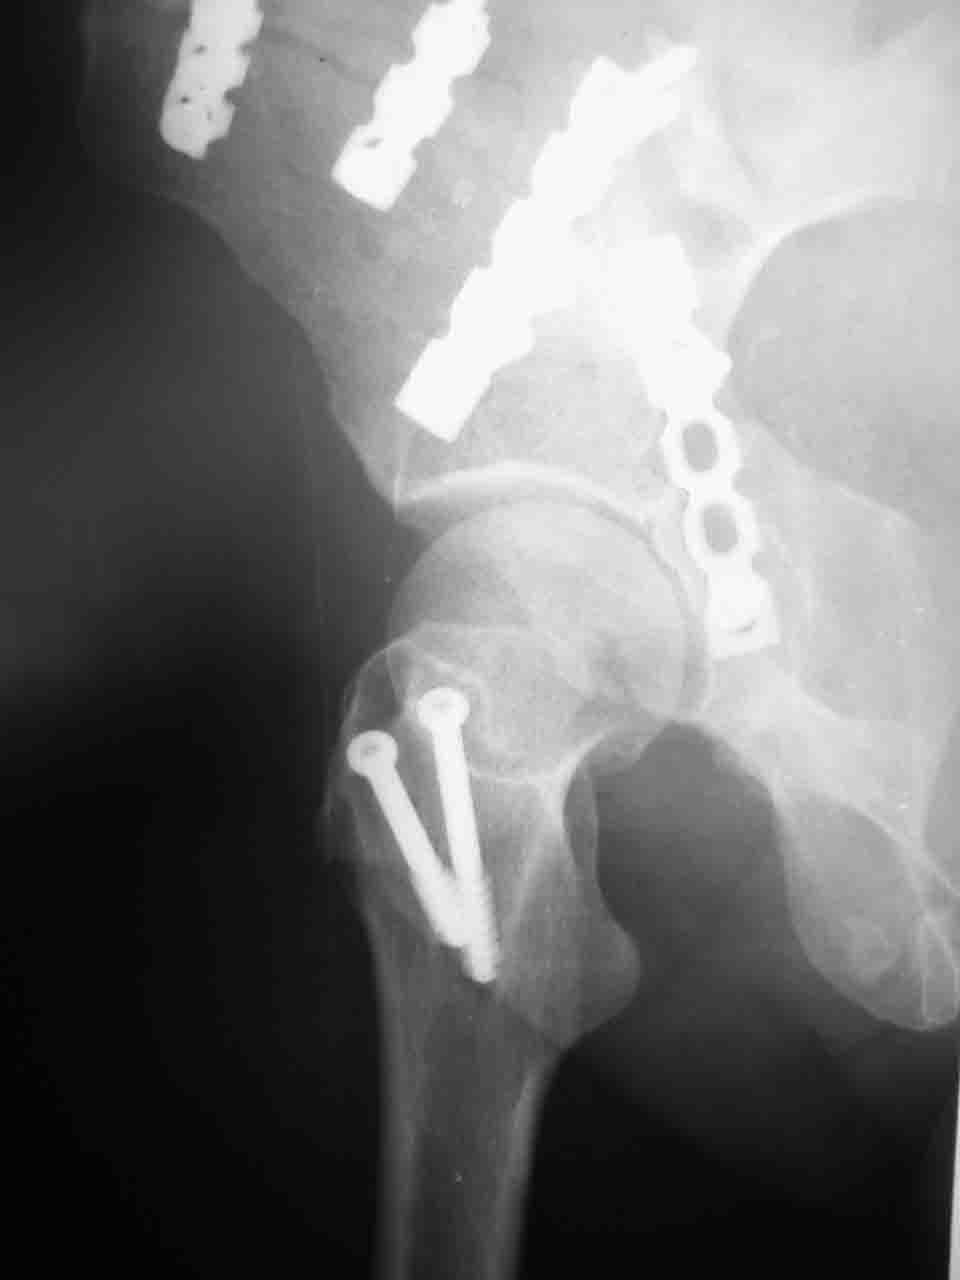

Re: Перелом вертлужной впадины

Смирнов Алексей 09 Ноябрь 2004, 01:17

Снимки и схема